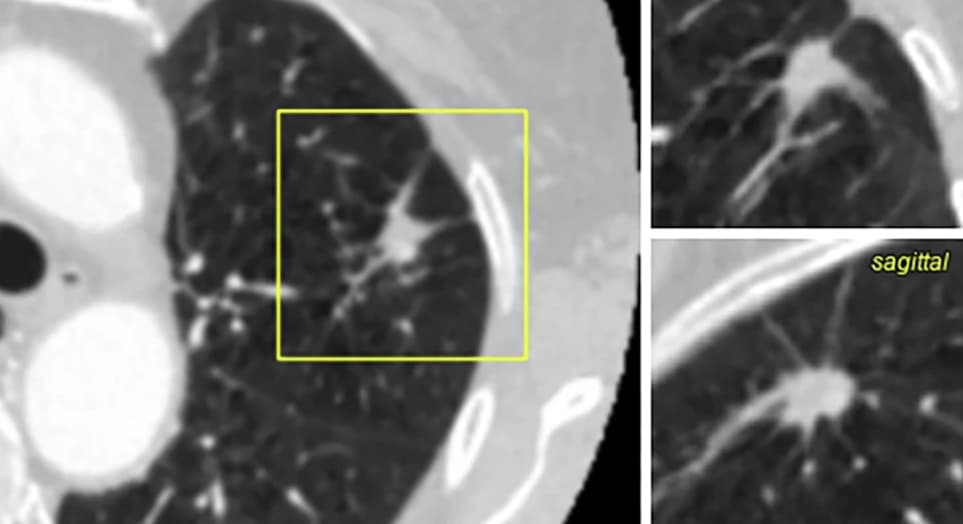

Une classification des nodules pulmonaires est classiquement réalisée à partir du modèle de Brock afin de réduire le nombre d’examens pour classer les nodules pulmonaires en TDM. Une étude publiée dans la Revue European Radiology compare les résultats obtenus par un modèle de deep learning à ceux du modèle de Brock. Un potentiel certain est identifié pour ce modèle, mais des ajustements nécessaires.